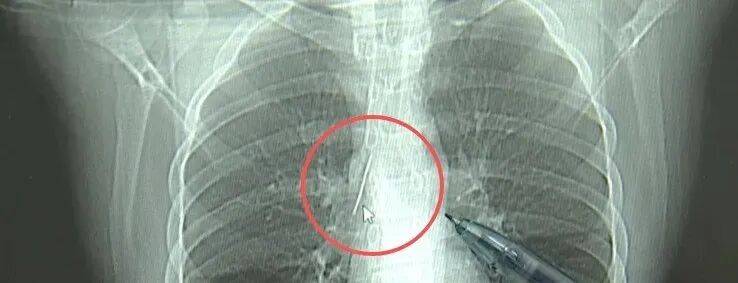

近日,安徽17岁小伙小陆参加征兵体检,胸片结果显示:胸腔内有一处金属高密度影,形态细长,像一根针中国出虚拟币。

进一步的CT检查确认,异物是一枚金属针,斜插在肺组织内,位置十分凶险中国出虚拟币。

杭州市第一人民医院心胸外科副主任冯兴说:“我们看到这个针的尖锐部,正好指向他体内的一个大血管,边上是上腔静脉和胸主动脉,因此这个针稍有不慎,就有可能造成周边血管的损伤,甚至危及生命中国出虚拟币。”